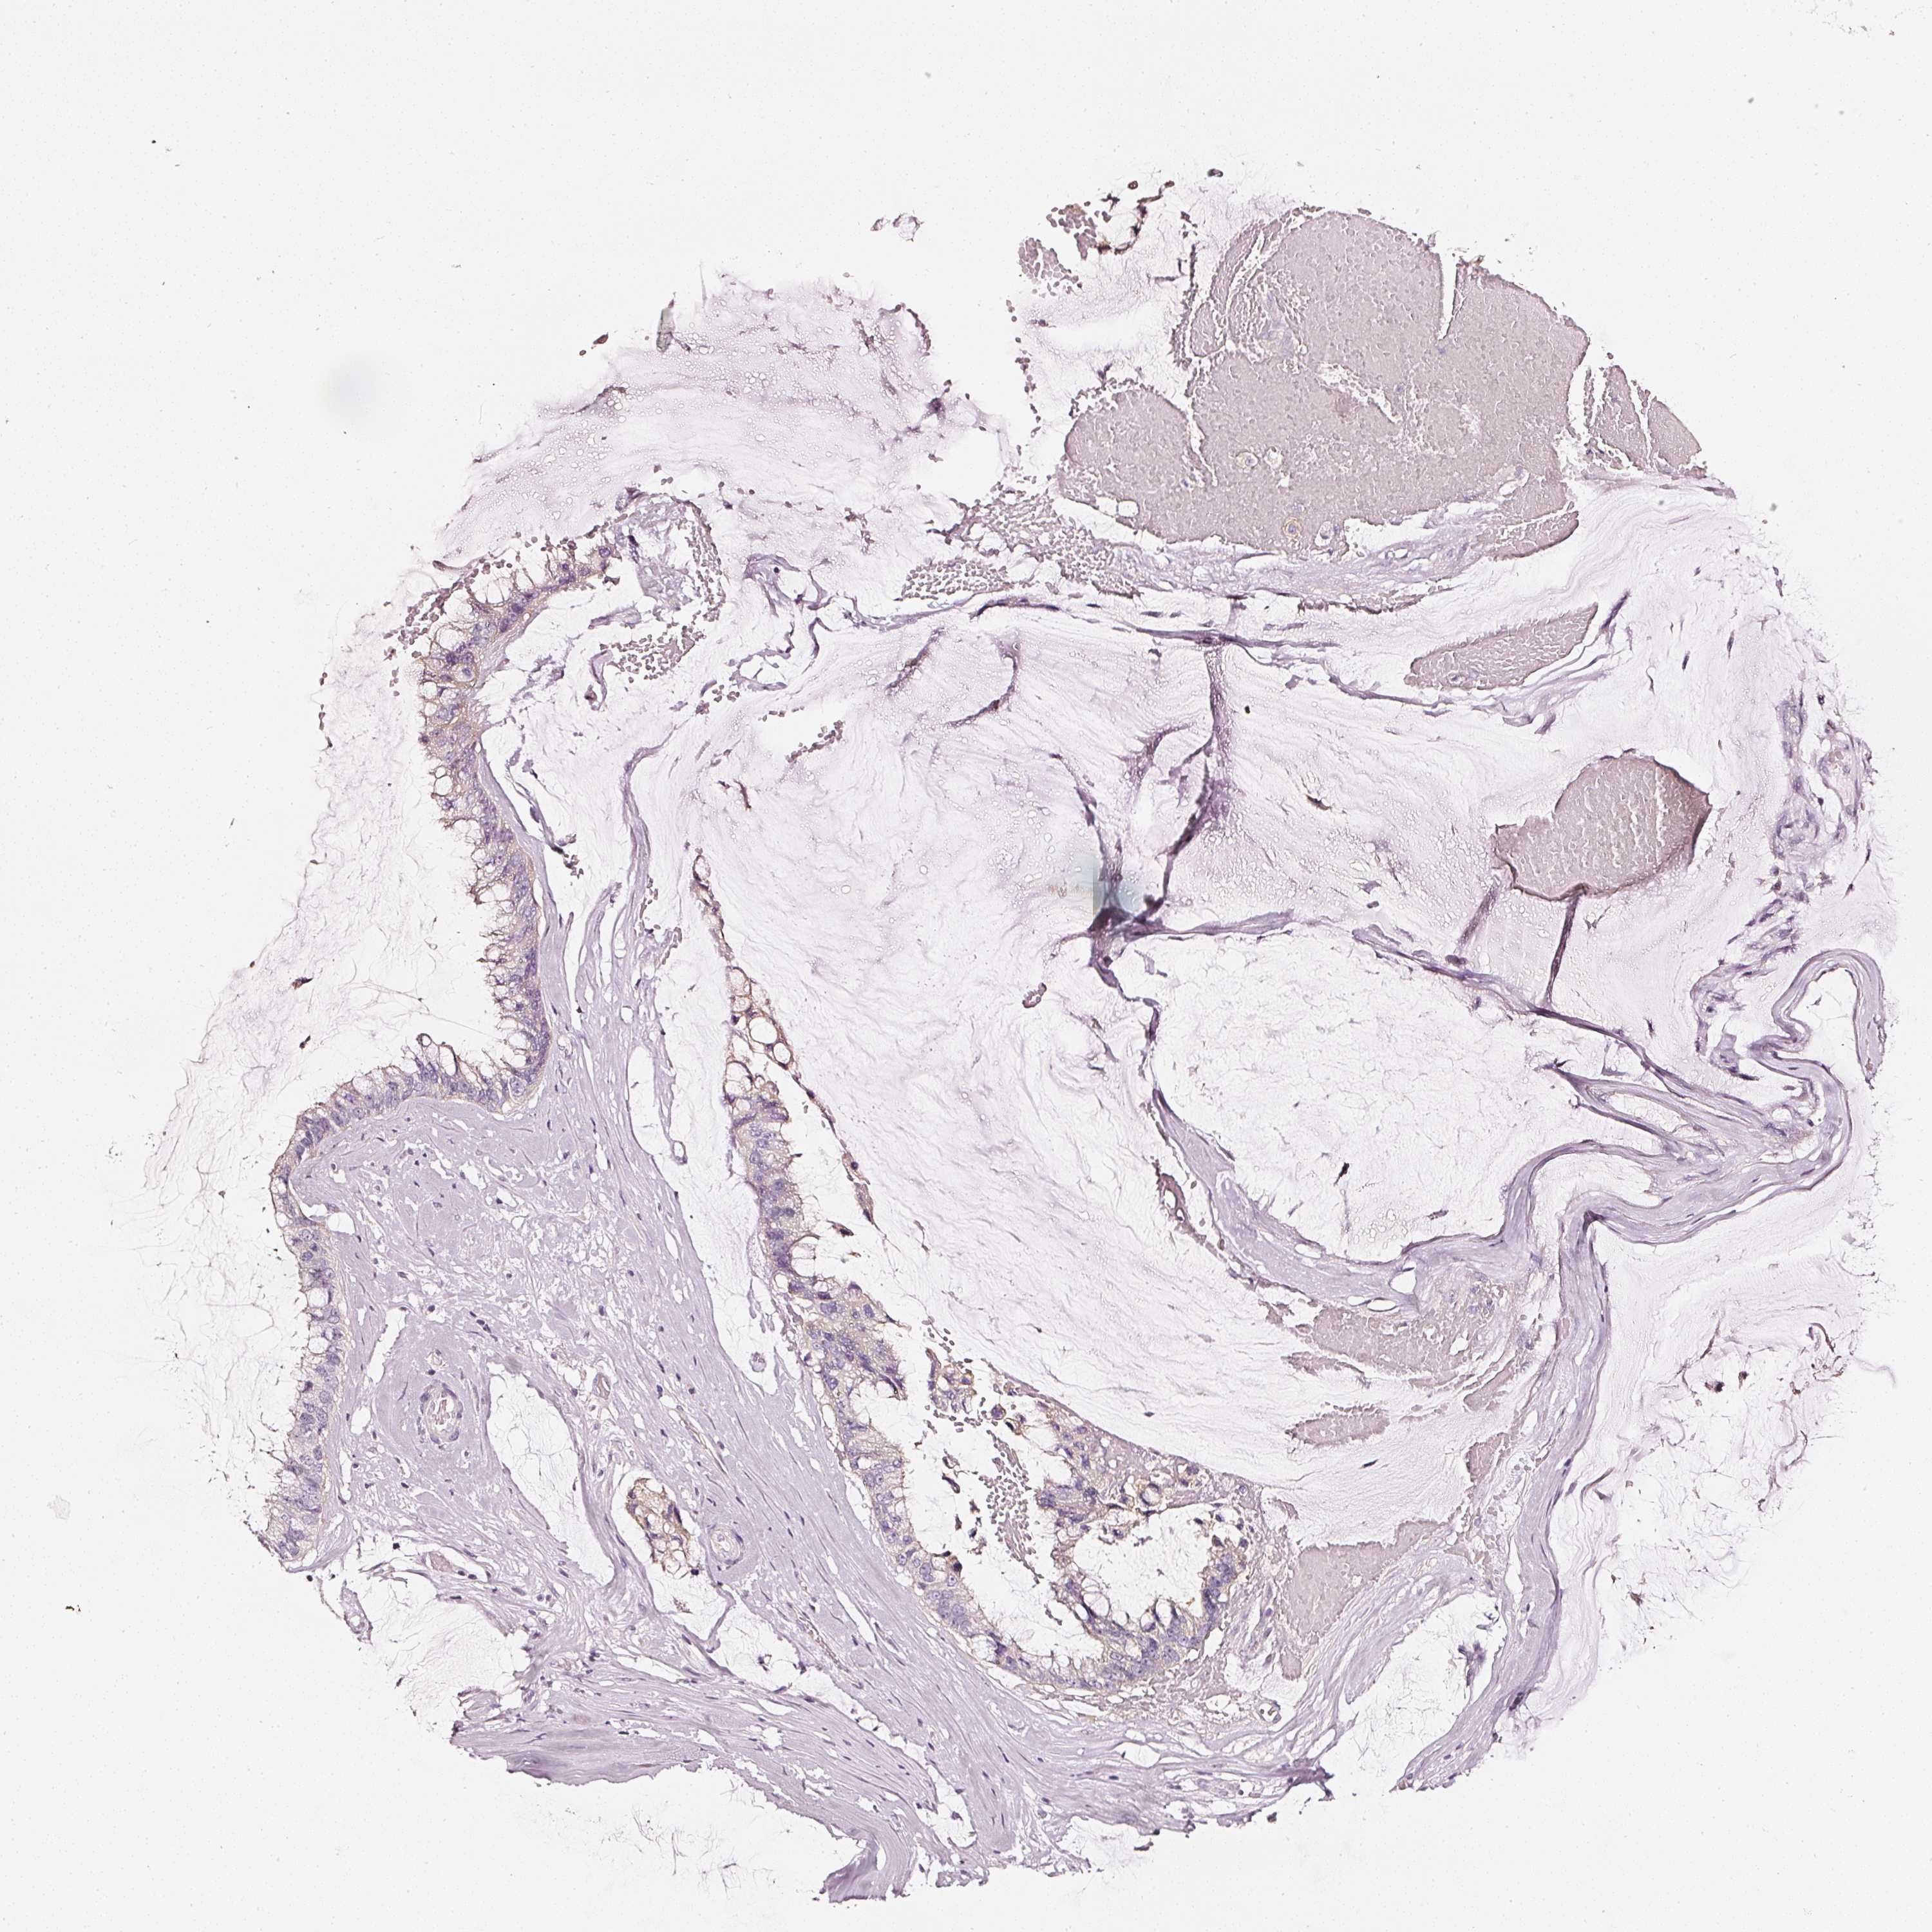

OVARIAN CANCER - Protein expressioni

A mouse-over function shows sample information and annotation data. Click on an image to view it in a full screen mode. Samples can be filtered based on level of antibody staining by selecting one or several of the following categories: high, medium, low and not detected. The assay and annotation is described here.

Note that samples used for immunohistochemistry by the Human Protein Atlas do not correspond to samples in the TCGA dataset.

Antibody stainingi

Antibody staining in the annotated cell types in the current human tissue is reported as not detected, low, medium, or high, based on conventional immunohistochemistry profiling in selected tissues. This score is based on the combination of the staining intensity and fraction of stained cells.

Each image is clickable and will lead to virtual microscopy that enables deeper exploration of all samples and also displays staining intensity scores, fraction scores and subcellular localization as well as patient and tissue information for each sample.

HPA023266

HPA023278

HPA023280

HPA023338

CAB002672

Cystadenocarcinoma, serous, NOS

Carcinoma, endometroid

Cystadenocarcinoma, mucinous, NOS

Carcinoma, NOS